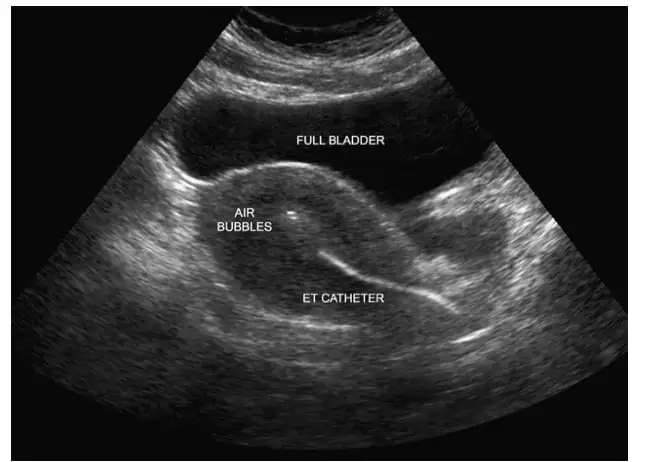

4. Embryo Transfer

Embryo Transfer

Healthy Embryo Injection

A selected healthy embryo is placed into the uterus.

This is a simple, painless procedure. No anesthesia needed.